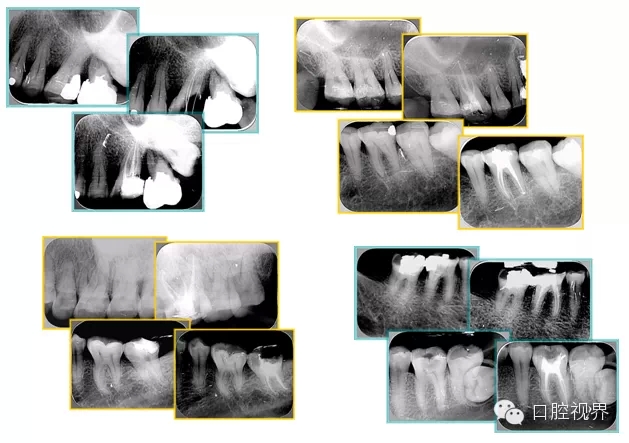

6. 術(shù)后 X 線片

術(shù)后 X 線片用來評定根管充填 長度、致密度(管壁清晰、側(cè)枝)等指標(biāo)。

左圖為根管充填術(shù)后 X 線片。圖中可見,根管充填較好。右下圖有白色小點(diǎn),為側(cè)方加壓導(dǎo)致糊劑擠出所致,表明根管充填比較致密。

致密、恰到好處的充填可去除干凈根管里感染灶,機(jī)體逐漸恢復(fù)。

多根牙時(shí)候需進(jìn)行偏移投照,正位投照無法說明具體哪根牙根管充填效果。